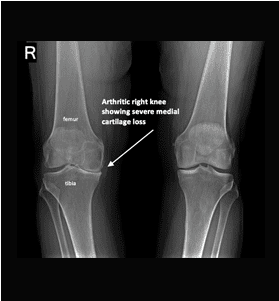

If nonsurgical treatments are not enough, you will need to have surgery. As with nonsurgical options, the purpose is to reduce pain, increase function, and generally reduce your rheumatoid arthritis symptoms. Patient satisfaction is a fundamental goal in treating arthritis and there are a number of options available, such as cartilage grafting, arthroscopic surgery, total or partial knee arthroplasty, and osteotomy.

If you are suffering from shoulder or knee arthritis in Los Angeles and would like to explore your treatment options, sign up for a consultation today with the best Beverly Hills osteoarthritis doctor by calling (310) 595-1030.